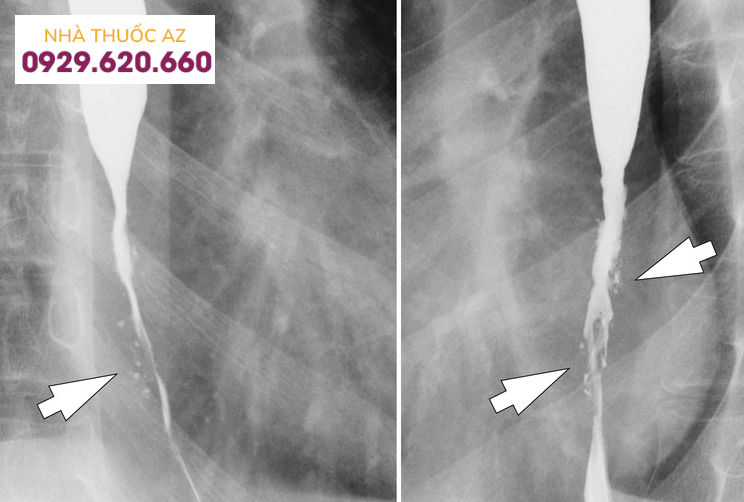

Đối với hẹp thực quản, theo một nghiên cứu được thực hiện trên bệnh nhân thực quản do bạch cầu ái toan, tỉ lệ phát hiện được hẹp bằng chụp Baryt lên đến 71% trong đó chủ yếu là hẹp ở đoạn dưới thực quản. Một nghiên cứu khác ghi nhận đoạn hẹp chủ yếu nằm ở phía trên hoặc thực quản đoạn ngực.

Đường kính của đoạn hẹp trung bình khoảng 1cm và vị trí hẹp ở phía đoạn thực quản trên/giữa có xu hướng dài hơn so với đoạn dưới. Tùy vị trí đoạn hẹp trên chụp Baryt vẫn cần cân nhắc đến các chẩn đoán phân biệt khác. Các nguyên nhân khác gây hẹp ở đoạn thực quản trên hoặc giữa bao gồm thực quản Barrett, xạ trị vùng trung thất, sử dụng một số loại thuốc như NSAID, quinidine, trong khi hẹp ở đoạn dưới thực quản có thể do viêmthực quản trào ngược. Cần chú ý những bệnh nhân có hình ảnh hẹp thực quản trên chụp Baryt thường có triệu chứng nuốt khó và đây chỉ là một dấu hiệu gợi ý, cần kết hợp nhiều yếu tố liên quan đến bệnh sử, triệu chứng lâm sàng, hình ảnh nội soi và mô bệnh học.Vòng thực quản cũng là hình ảnh hay gặp với nhiều thuật ngữ được sử dụng như “khí quản hóa thực quản” hay “thực quản dạng vòng”. Vị trí và sự phân bố của các vòng thực quản rất khác nhau trên nội soi, có thể ở các đoạn của thực quản hoặc phân bổ lan tỏa nhiều chỗ. Đôi khi những vòng này có thể gây hẹp khiến dây sợi khó đưa qua được. Trên chụp Baryt, các vòng này thường nhiều, hay xuất hiện gần nhau, có dạng đồng tâm dọc theo lòng thực quản.